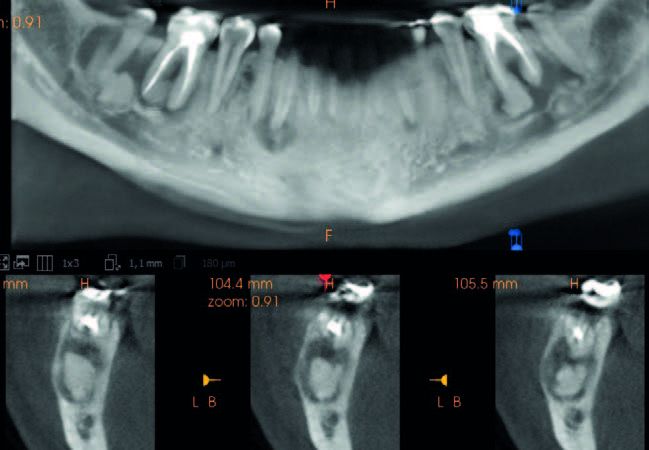

En 2023 se llevó a cabo una nueva evaluación radiográfica, complementada con un CBCT (Figura 3). En el estudio se identificaron áreas hiperdensas bien definidas, correspondientes a las regiones de los dientes 36, 43, 46 y 47. Estas áreas estaban rodeadas por un halo radiotransparente de forma irregular, sugiriendo la presencia de material mineralizado dentro de un tejido fibroso menos denso. Esas características radiográficas eran compatibles con un patrón intermedio de DCOF, que incluye la transición típica desde una fase predominantemente radiotransparente a una fase mixta.